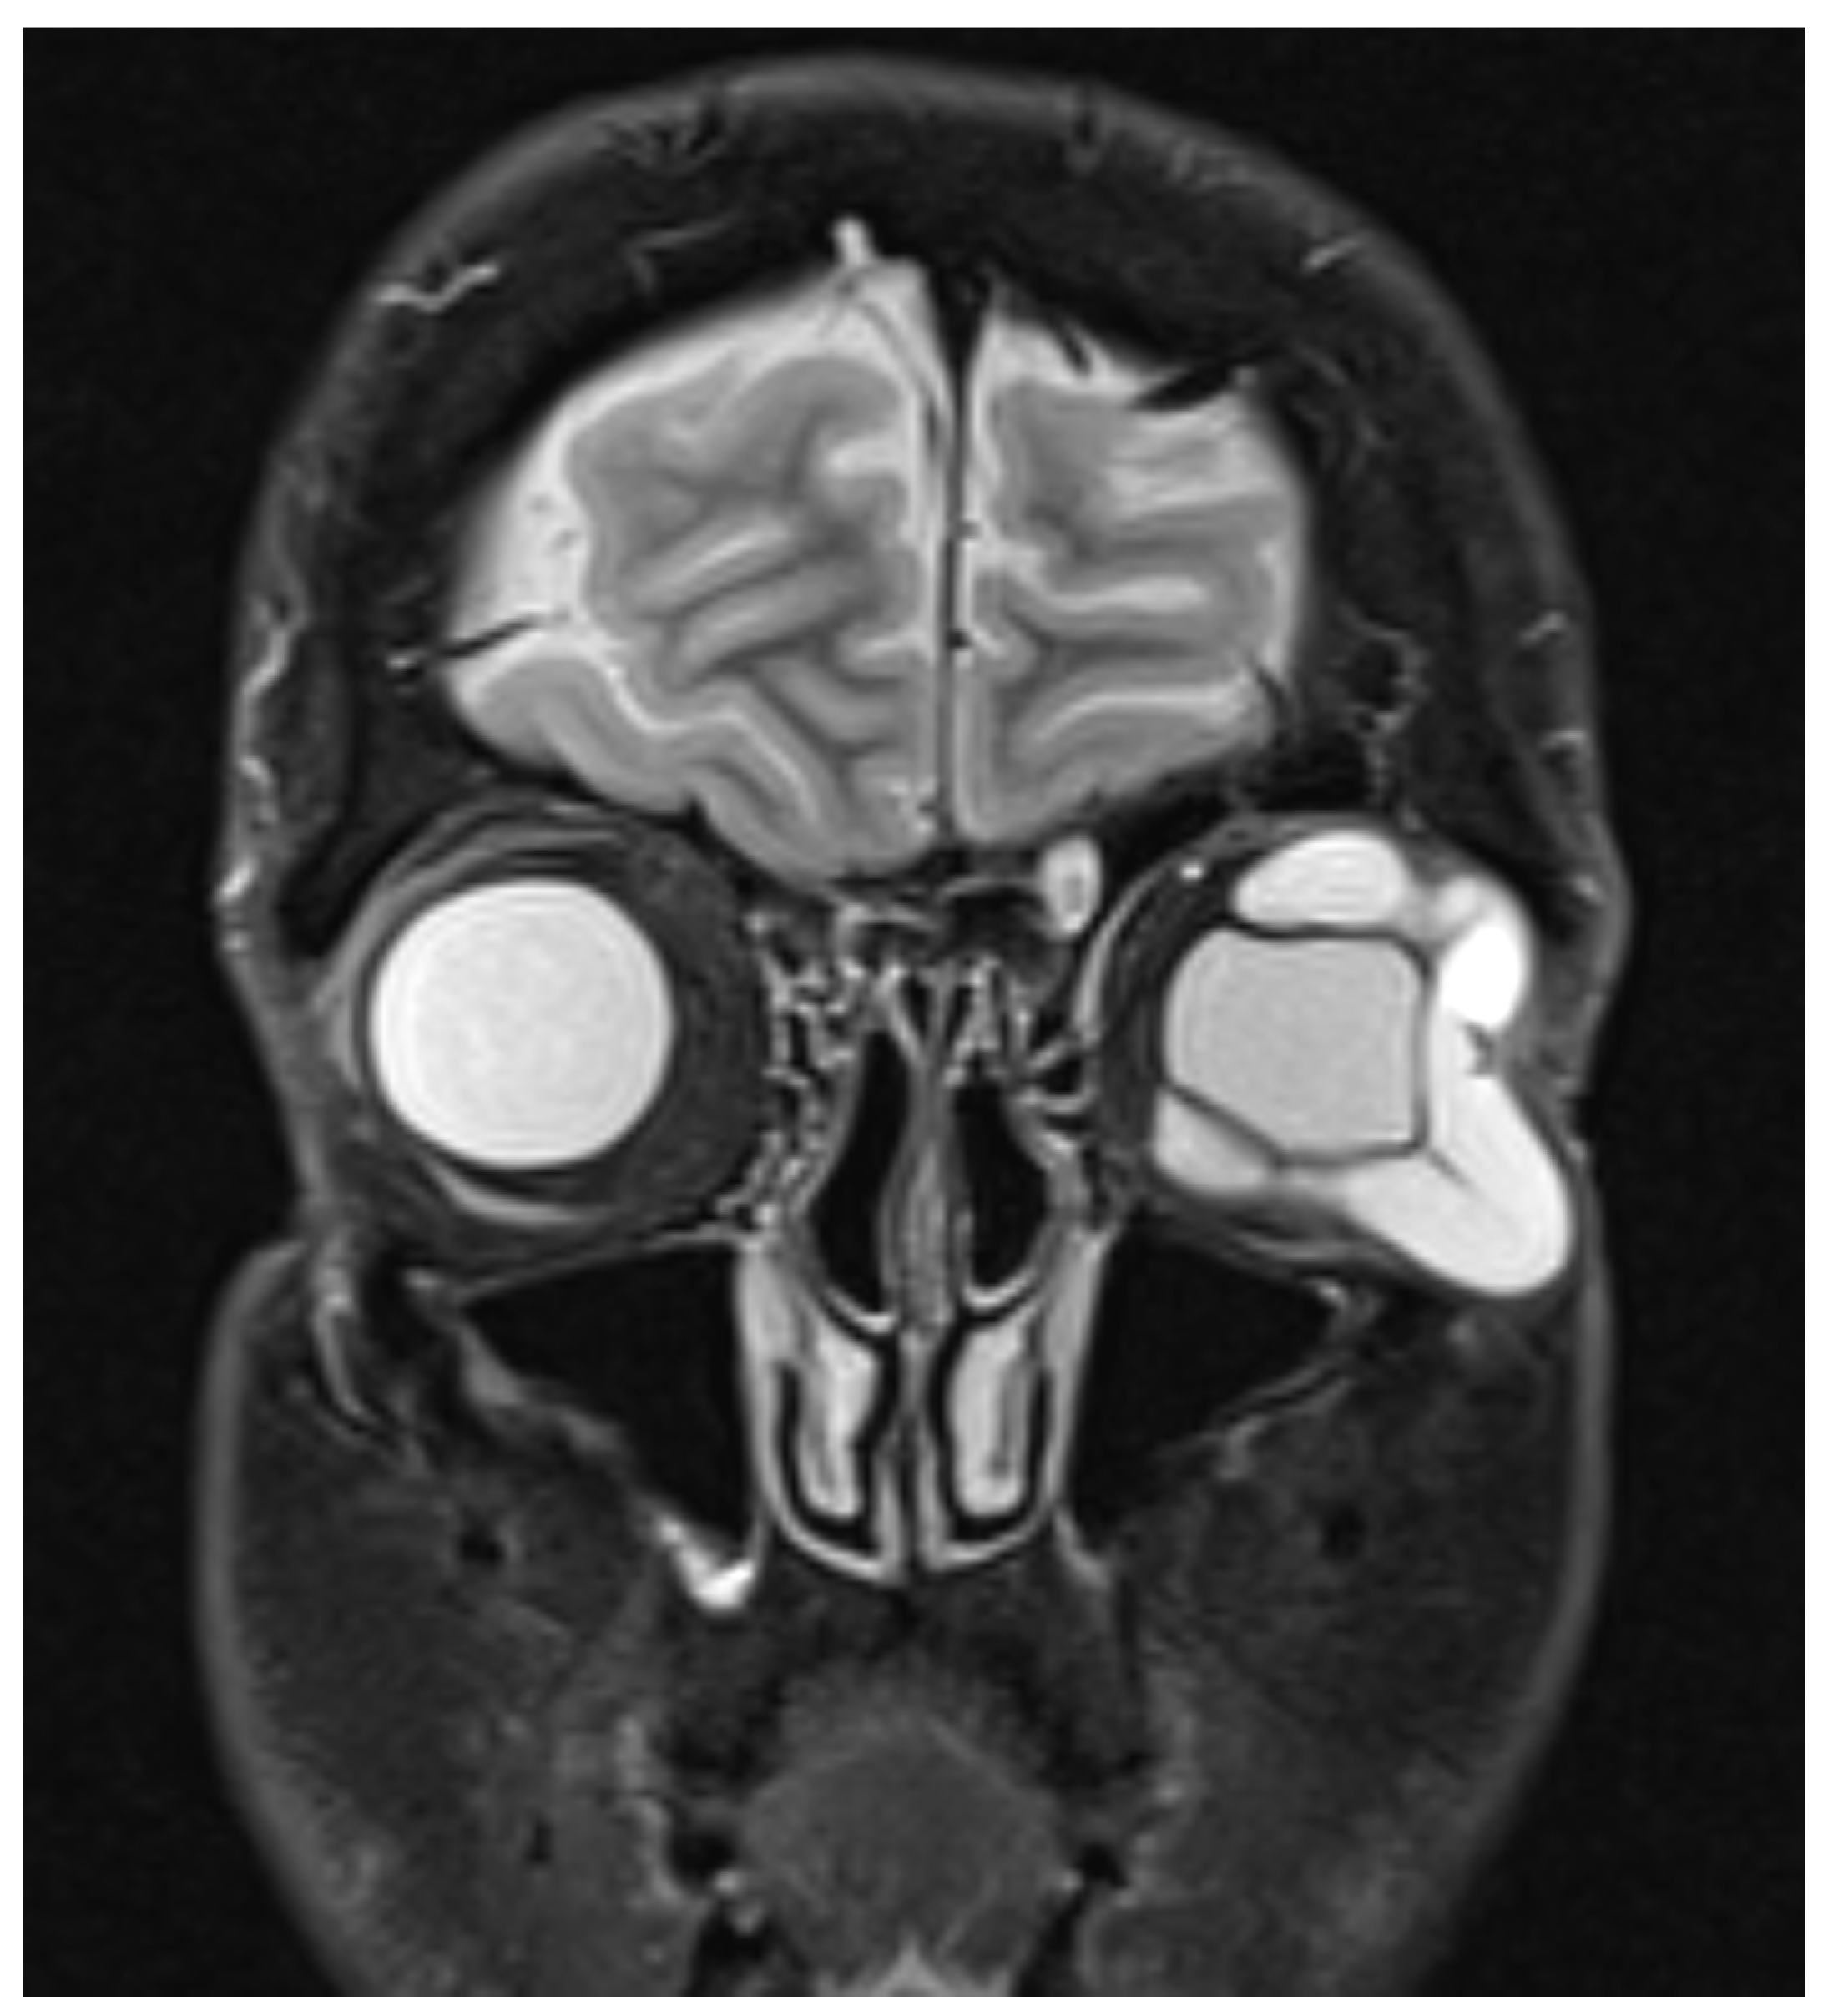

Figure 1.

Coronal section of T2-weighted sequence of magnetic resonance imaging (MRI) of the orbits showing large tubular lesion in the extraconal space of the left orbit sparing the medial portion of the orbit with globe distortion.